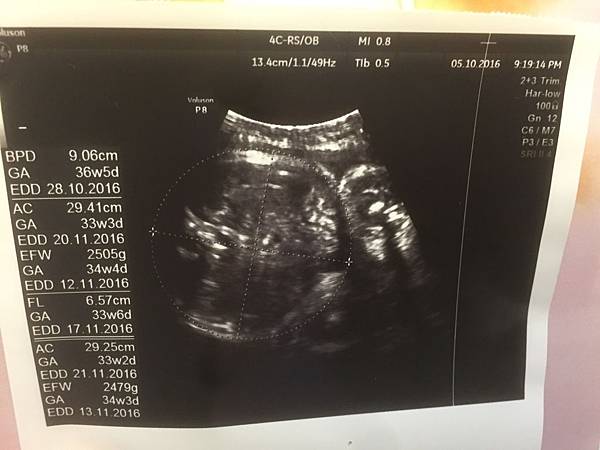

36週產檢最緊張的就是寶包重量

好險皇天不負苦心人

醫生說有2480公克了!

這兩週進步500!我聽到真的好開心!